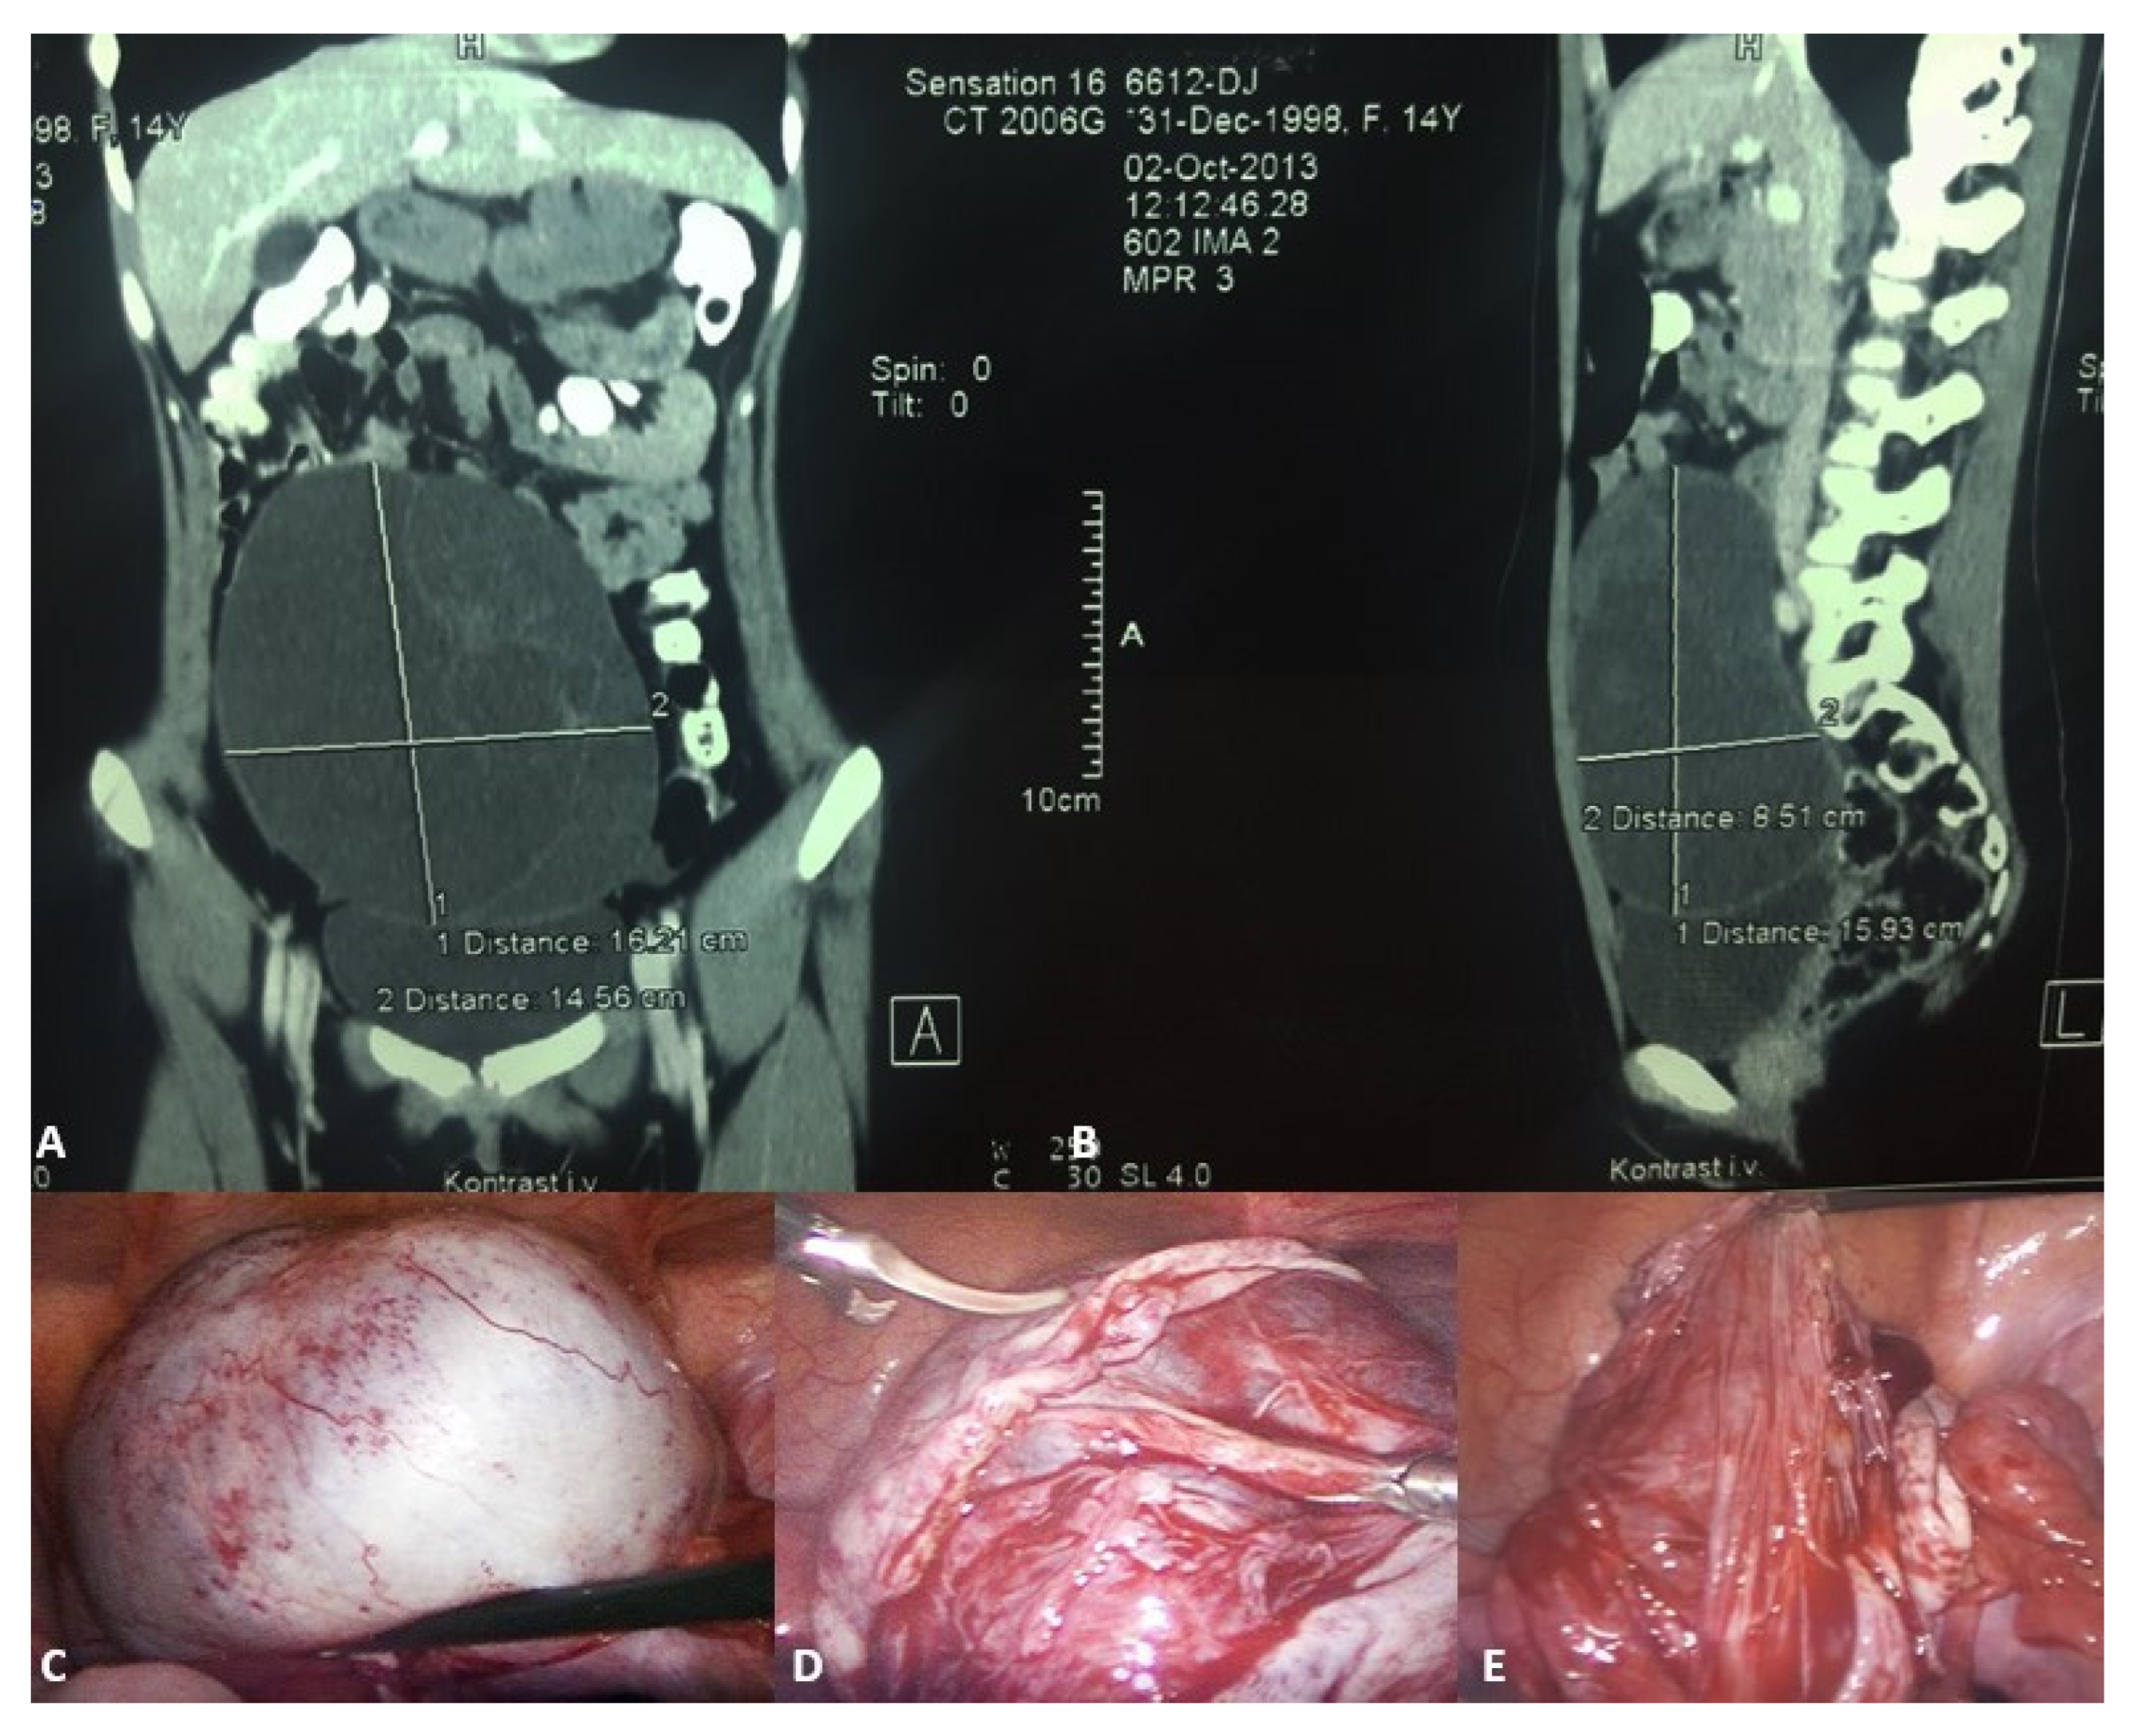

Figure 3.

A 14-year-old girl presented with intermittent abdominal pain, loss of appetite, and a palpable abdominal mass. (A) Multislice computed tomography revealed a giant right abdominal ovarian cyst measuring 16.2 × 14.6 cm; (B) The cystic mass filled the entire lower abdomen and was pressing on the surrounding structures; (C) Laparoscopic examination revealed a giant ovarian cyst; (D) The ovarian cortex was opened, 2 L of clear contents were aspirated; (E) A laparoscopic cystectomy with ovarian sparing was performed. A pathohistological examination revealed a simple ovarian cyst. Source: Archive of the Department of Pediatric Surgery, University Hospital of Split.